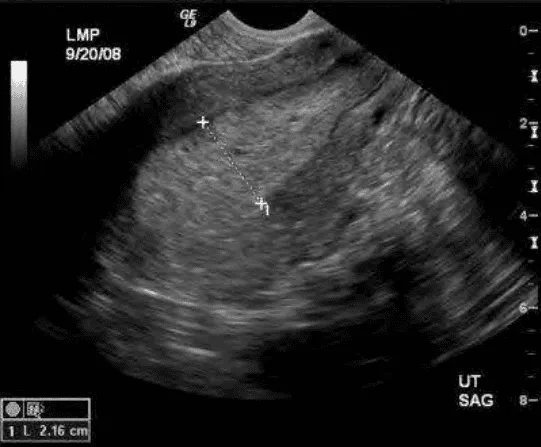

Phần tiêu đề “Chẩn đoán hình ảnh”Siêu âm là chỉ định đầu tay. Thời điểm tối ưu ngay sau sạch kinh để đo độ dày nội mạc mỏng nhất (thông thường < 4-5 mm). Đặc điểm cần ghi nhận:

- Độ dày nội mạc ≥ 5 mm ở phụ nữ quanh mãn kinh cần đánh giá thêm.

- Hình thái nội mạc đều mỏng, lòng tử cung không có khối, không có kẽ tăng tín hiệu nhấp nhô.

Hình ảnh “Tăng sinh nội mạc tử cung: Nội mạc dày 21.6 mm đầu chu kỳ là bất thường. Không thể chẩn đoán cơ năng khi có hình ảnh này”.